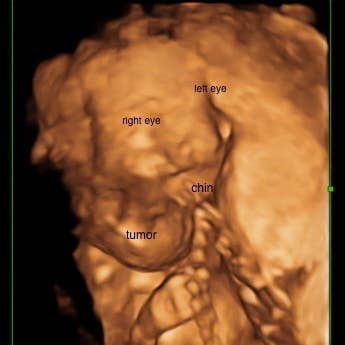

In February 2016, Paradiso was 18 weeks pregnant with her daughter Omara when doctors discovered a mass on the baby’s neck during a routine ultrasound.

The ultrasound showed a bubble on Omara’s neck, which she said doctors believed was a rare tumor called a “teratoma” but wouldn’t know more until they did an MRI.

Three weeks later, Paradiso got an MRI that confirmed their worst fears: The tumor had tripled in size and was growing into her head, chest, lungs, and eyes. It was inoperable.

However, doctors learned from the MRI that Omara’s case was far worse, and the tumor was growing inside her brain as well. “It was aggressive lymphangioma, and it was three times the size of her head by now and they were 99% sure it was fatal,” Paradiso said.